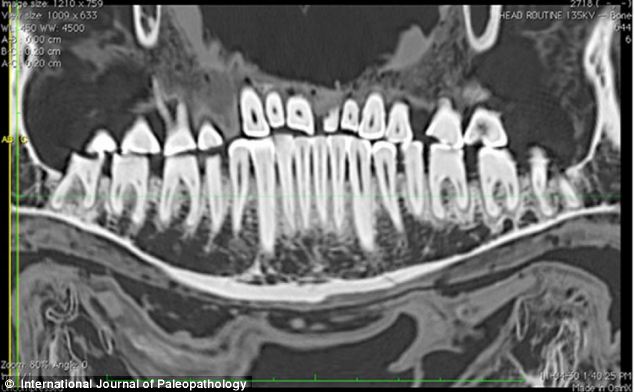

相比過去的研究器材,CT掃描儀使研究團隊能夠更清晰詳盡地觀察填充物。

CT片顯示了木乃伊左邊第一顆門牙(左圖)和右邊第二顆門牙(右圖)的磨損狀況。